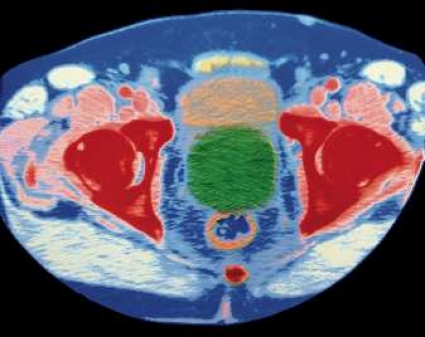

Denna svenska metod går ut på att behandlingen styrs av den temperatur som man med en nål mäter upp inne i prostatakörteln under själva behandlingen, vilket i sin tur möjliggör optimerad behandling av den enskilde individen. Uppmuntrade av mycket goda preliminära resultat ville vi på ett kontrollerat sätt undersöka om metoden verkligen skulle kunna mäta sig med vanlig operation, dvs transuretral prostataresektion, TURP, som ju länge har ansetts som etablerad standard.

I en randomiserad, kontrollerad multicenterstudie på 154 patienter jämförde vi därför PLFT (CoreTherm) med TURP. Studien pågick under åren 2000–2006. Förhållandet mellan antalet inkluderade patienter var 2:1, och 100 patienter ingick i PLFT-gruppen.